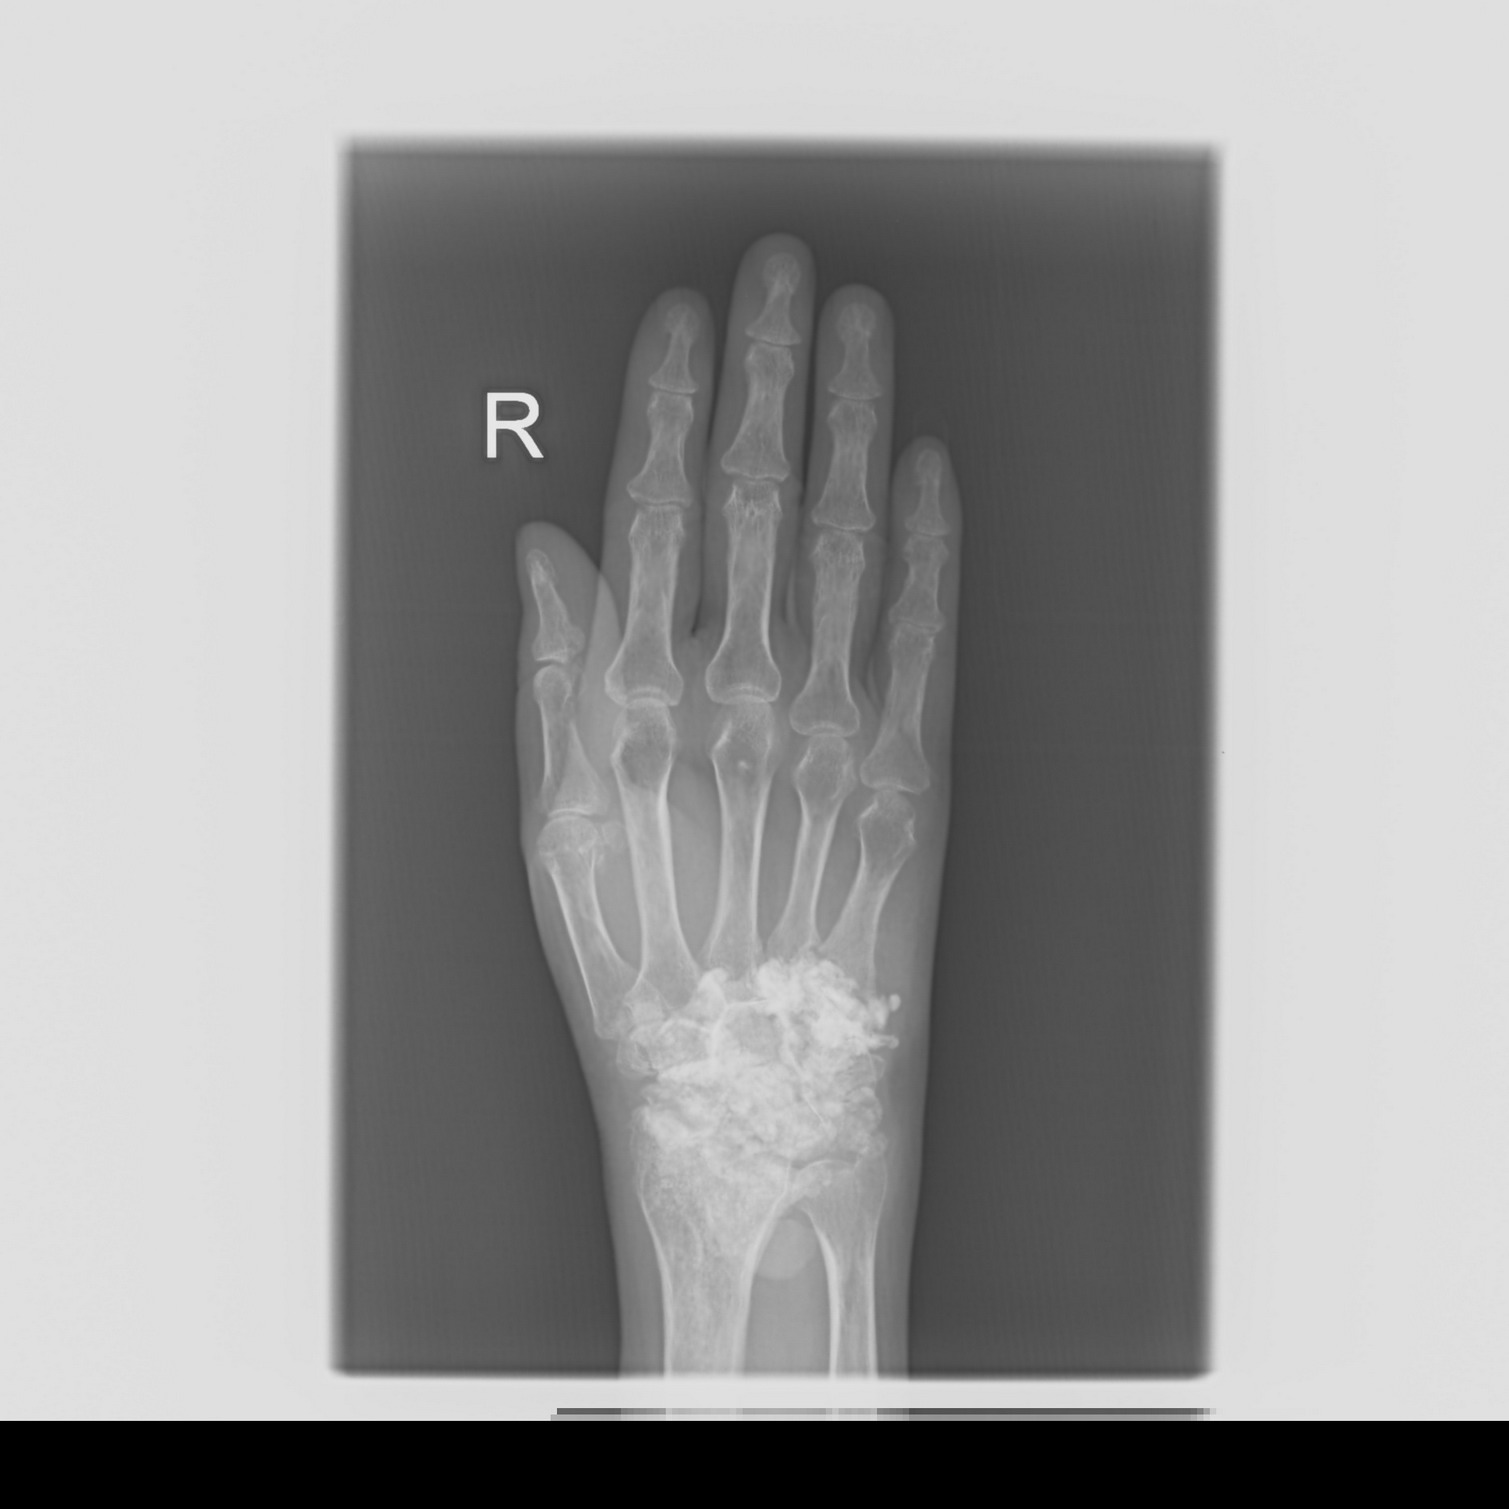

标题: X3291:腕关节处广泛钙化/骨化影 [打印本页]

活动障碍,疼痛,有过手术史,病理病人自述不清,滑膜骨软骨瘤病?

如果不是体外的异物,可考虑滑膜骨软骨瘤病,因为发生在腕关节的确少见。

腕部广泛致密影,暴风雪样,,,支持2楼

滑膜骨软骨瘤病是一种病因尚不明的发生于滑膜、滑囊或腱内的软骨性、纤维骨性或骨软骨小体的较少见的关节疾患。

本病发病机制不明,分为原发性和继发性两大类,原发性中以胚胎学说为主。即残存胚胎组织活化,增生,引起滑膜化生,继发性指以炎症外伤等引起的骨性关节面碎裂,刺激关节滑膜化生引起关节内游离体形成。目前认为是滑膜受创伤或炎症刺激后的反应性增生所致。

游离体脱落于关节腔内,失去血液供应后,外周的软骨犹如包壳,依靠滑液可以继续生存生长,形成较多较大的瘤体。

有学者认为本病偶有对称关节受累,故日常工作中发现一侧关节发病的情况下,应尽可能加照对侧关节的正侧位片。x线上即使只发现1枚典型的游离体影像仍需考虑本病可能性。

在鉴别诊断上,就平片而言,应排除关节外的钙化或骨化,如骨瘤,神经性关节病的钙化,血肿性钙化及钙化性关节周围炎以及破伤风患者的骨关节旁骨化等。其次应考虑是否为关节内的骨折碎片,骨脱落后听游离体或剥脱性软骨炎。就关节造影而言,需与色素沉着绒毛结节性滑膜炎,乔木状脂肪瘤,滑膜血管瘤等病鉴别。

肿瘤样钙质沉着?滑膜骨软骨瘤病不支持。硬皮病也有可能。